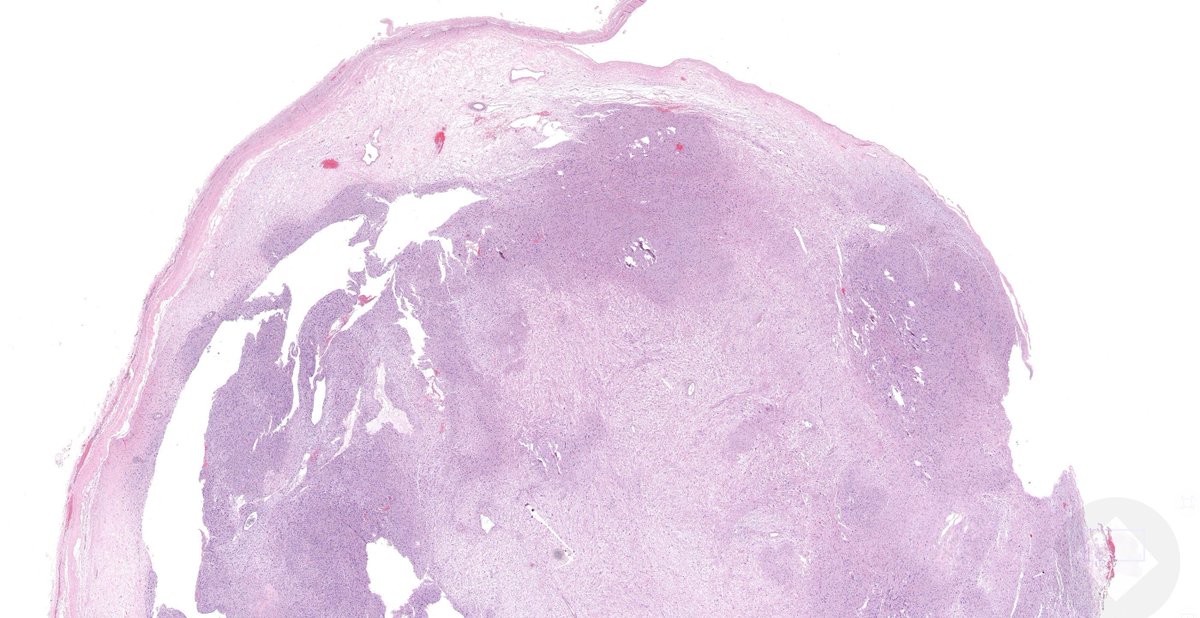

35 yo woman with 4 cm popliteal mass. Your diagnosis?

Answer ✅ youtu.be/r0bbLP6S600?si…

Digital slide 🔬 kikoxp.com/posts/11804

More info: kikoxp.com/posts/12126

#pathology #pathologists #pathTwitter #dermpath #dermatology #dermtwitter #BSTpath